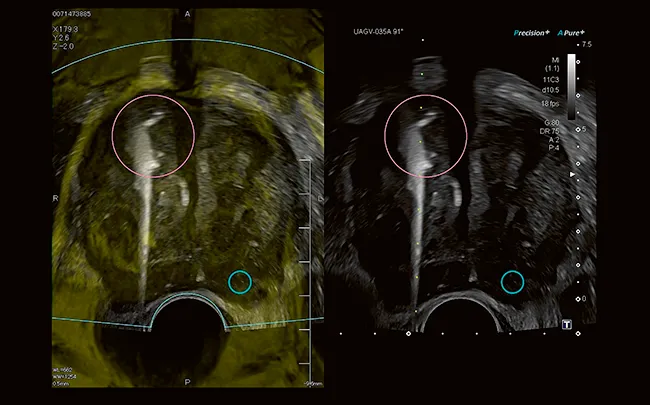

Smart Fusion объединяет ультразвук в реальном времени с ранее полученными данными КТ, МРТ или УЗИ, позволяя легко идентифицировать и сравнивать очаги поражения и безопасно ориентироваться в сложной анатомии.

Для комплексного обследования Smart Fusion позволяет работать в нескольких режимах визуализации, включая цветную допплерографию и CEUS. Лаконичный четырехзонный дисплей отображает изображение ультразвука в реальном времени синхронно с несколькими видами предварительно загруженных данных.

Интеллектуальная навигация помогает надежно и достоверно направлять кончики игл. Виртуальные линии биопсии с цветовой маркировкой позволяют легко отслеживать иглы как на ультразвуковом исследовании в режиме реального времени, так и на смежном сращенном изображении.

Технология Canon BEAM обеспечивает более четкую визуализацию биопсийных игл в режиме реального времени. Функция работает со всеми распространенными размерами игл и полностью автоматически выбирает оптимальное усиление.

Простой в использовании пакет Fusion от Aplio обеспечивает сверхбыструю загрузку и регистрацию объема. Теперь функция также поддерживает 3D-картирование биопсии предстательной железы.